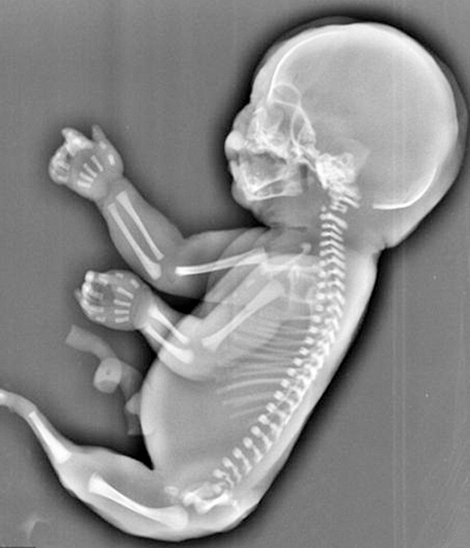

An ultrasound scan reportedly showing a young mother in China carrying a 'mermaid-like' foetus

According to a shocking report by Dailymail, the lady's scans showed that her unborn child did not have two legs, but instead had a 'tail' like growth, and also did not have a bladder and had a stunted liver.

It was learnt that doctors at the hospital told the woman that the foetus was suffering from a condition known as sirenomelia, or 'Mermaid Syndrome', a rare congenital deformity in which the legs are fused together, giving them the appearance of a mermaid's tail.